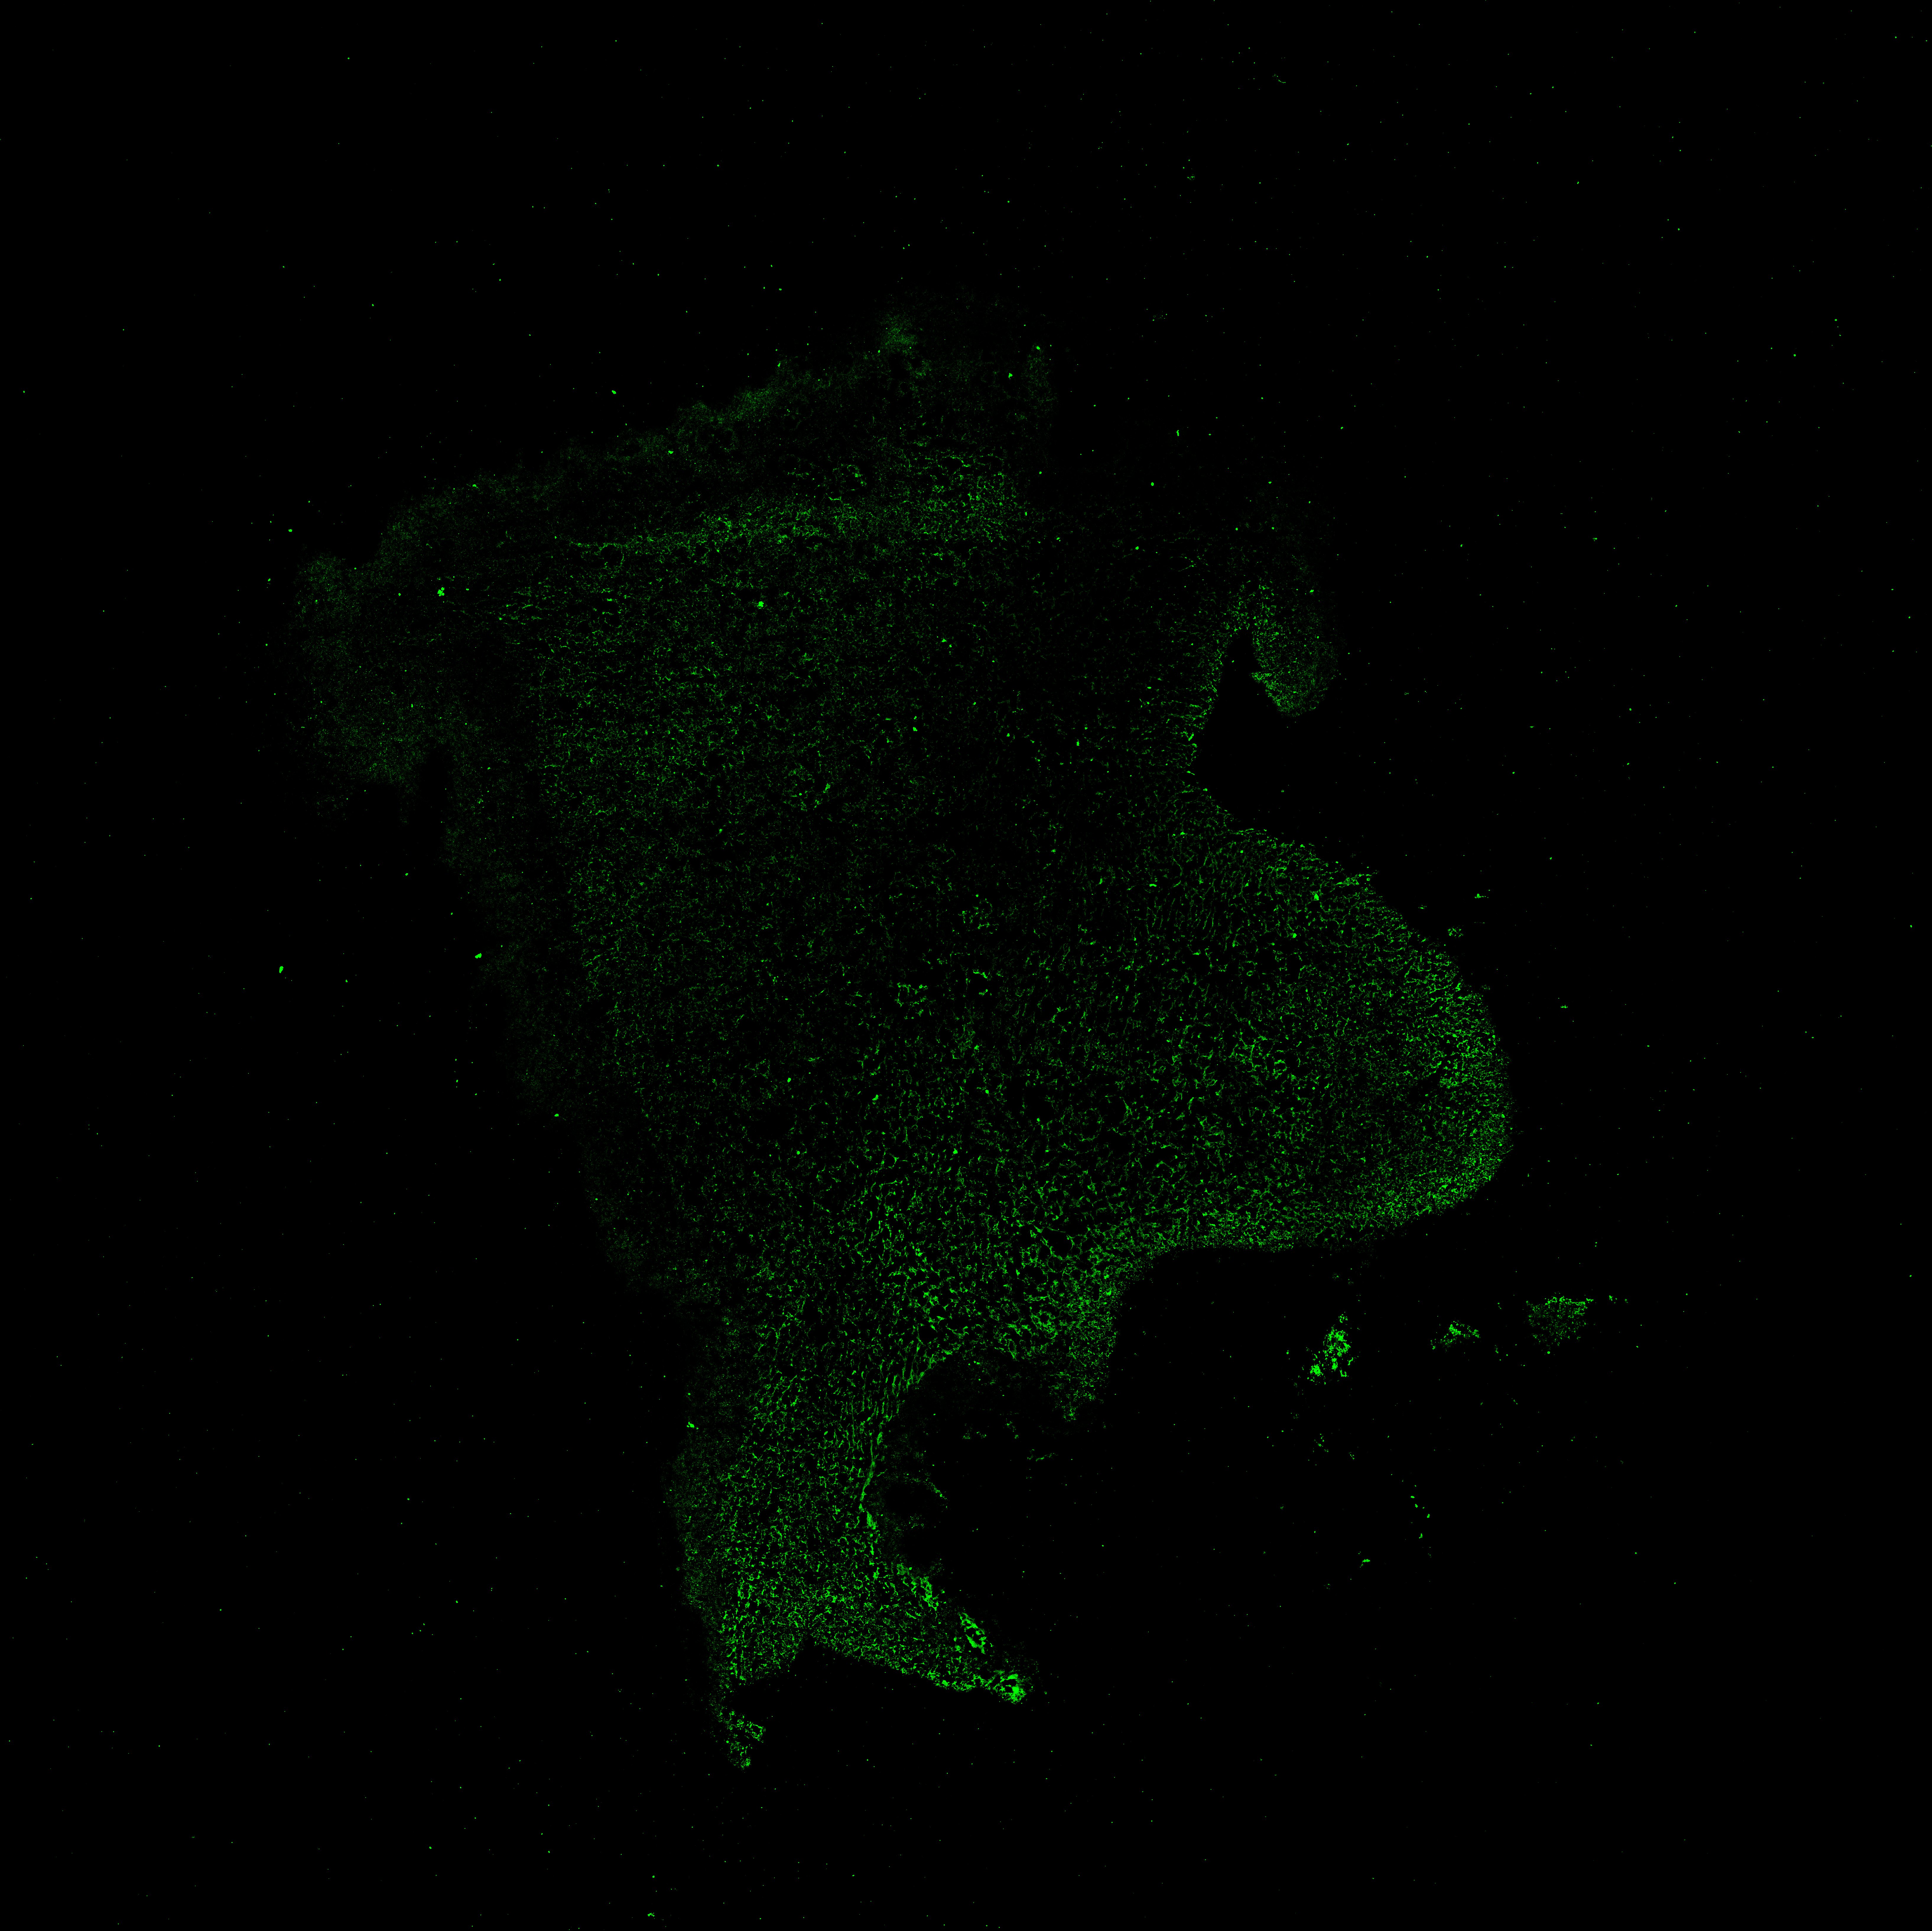

An anatomical analysis of the developing human midbrain from 6 post-conceptional weeks (PCW) to 22 PCW reveals increased tissue complexity, characterized by the emergence of dopaminergic nuclei, as highlighted by immunofluorescence analysis for tyrosine hydroxylase (TH).

MAP2

6PCW human midbrain

TH